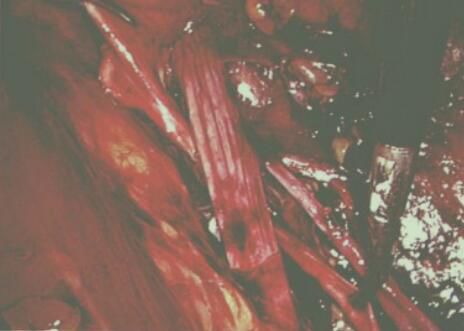

泌尿外科團(tuán)隊(duì)術(shù)中探查確診為腔靜脈后輸尿管,該病例系我院第一例,腹腔鏡下離斷輸尿管及修復(fù)重建,腹膜后腔操作空間較小,操作下方易傷及腔靜脈,手術(shù)風(fēng)險(xiǎn)高,手術(shù)難度巨大

在科室主任李世江的帶領(lǐng)下,步步為營進(jìn)行手術(shù)攻堅(jiān),顯露腎盂及上段輸尿管,向下游離下腔靜脈并明確輸尿管和下腔靜脈之關(guān)系。于近端輸尿管轉(zhuǎn)向處離斷輸尿管,將下腔靜脈后段輸尿管一位置下腔靜脈前面進(jìn)行端端吻合。